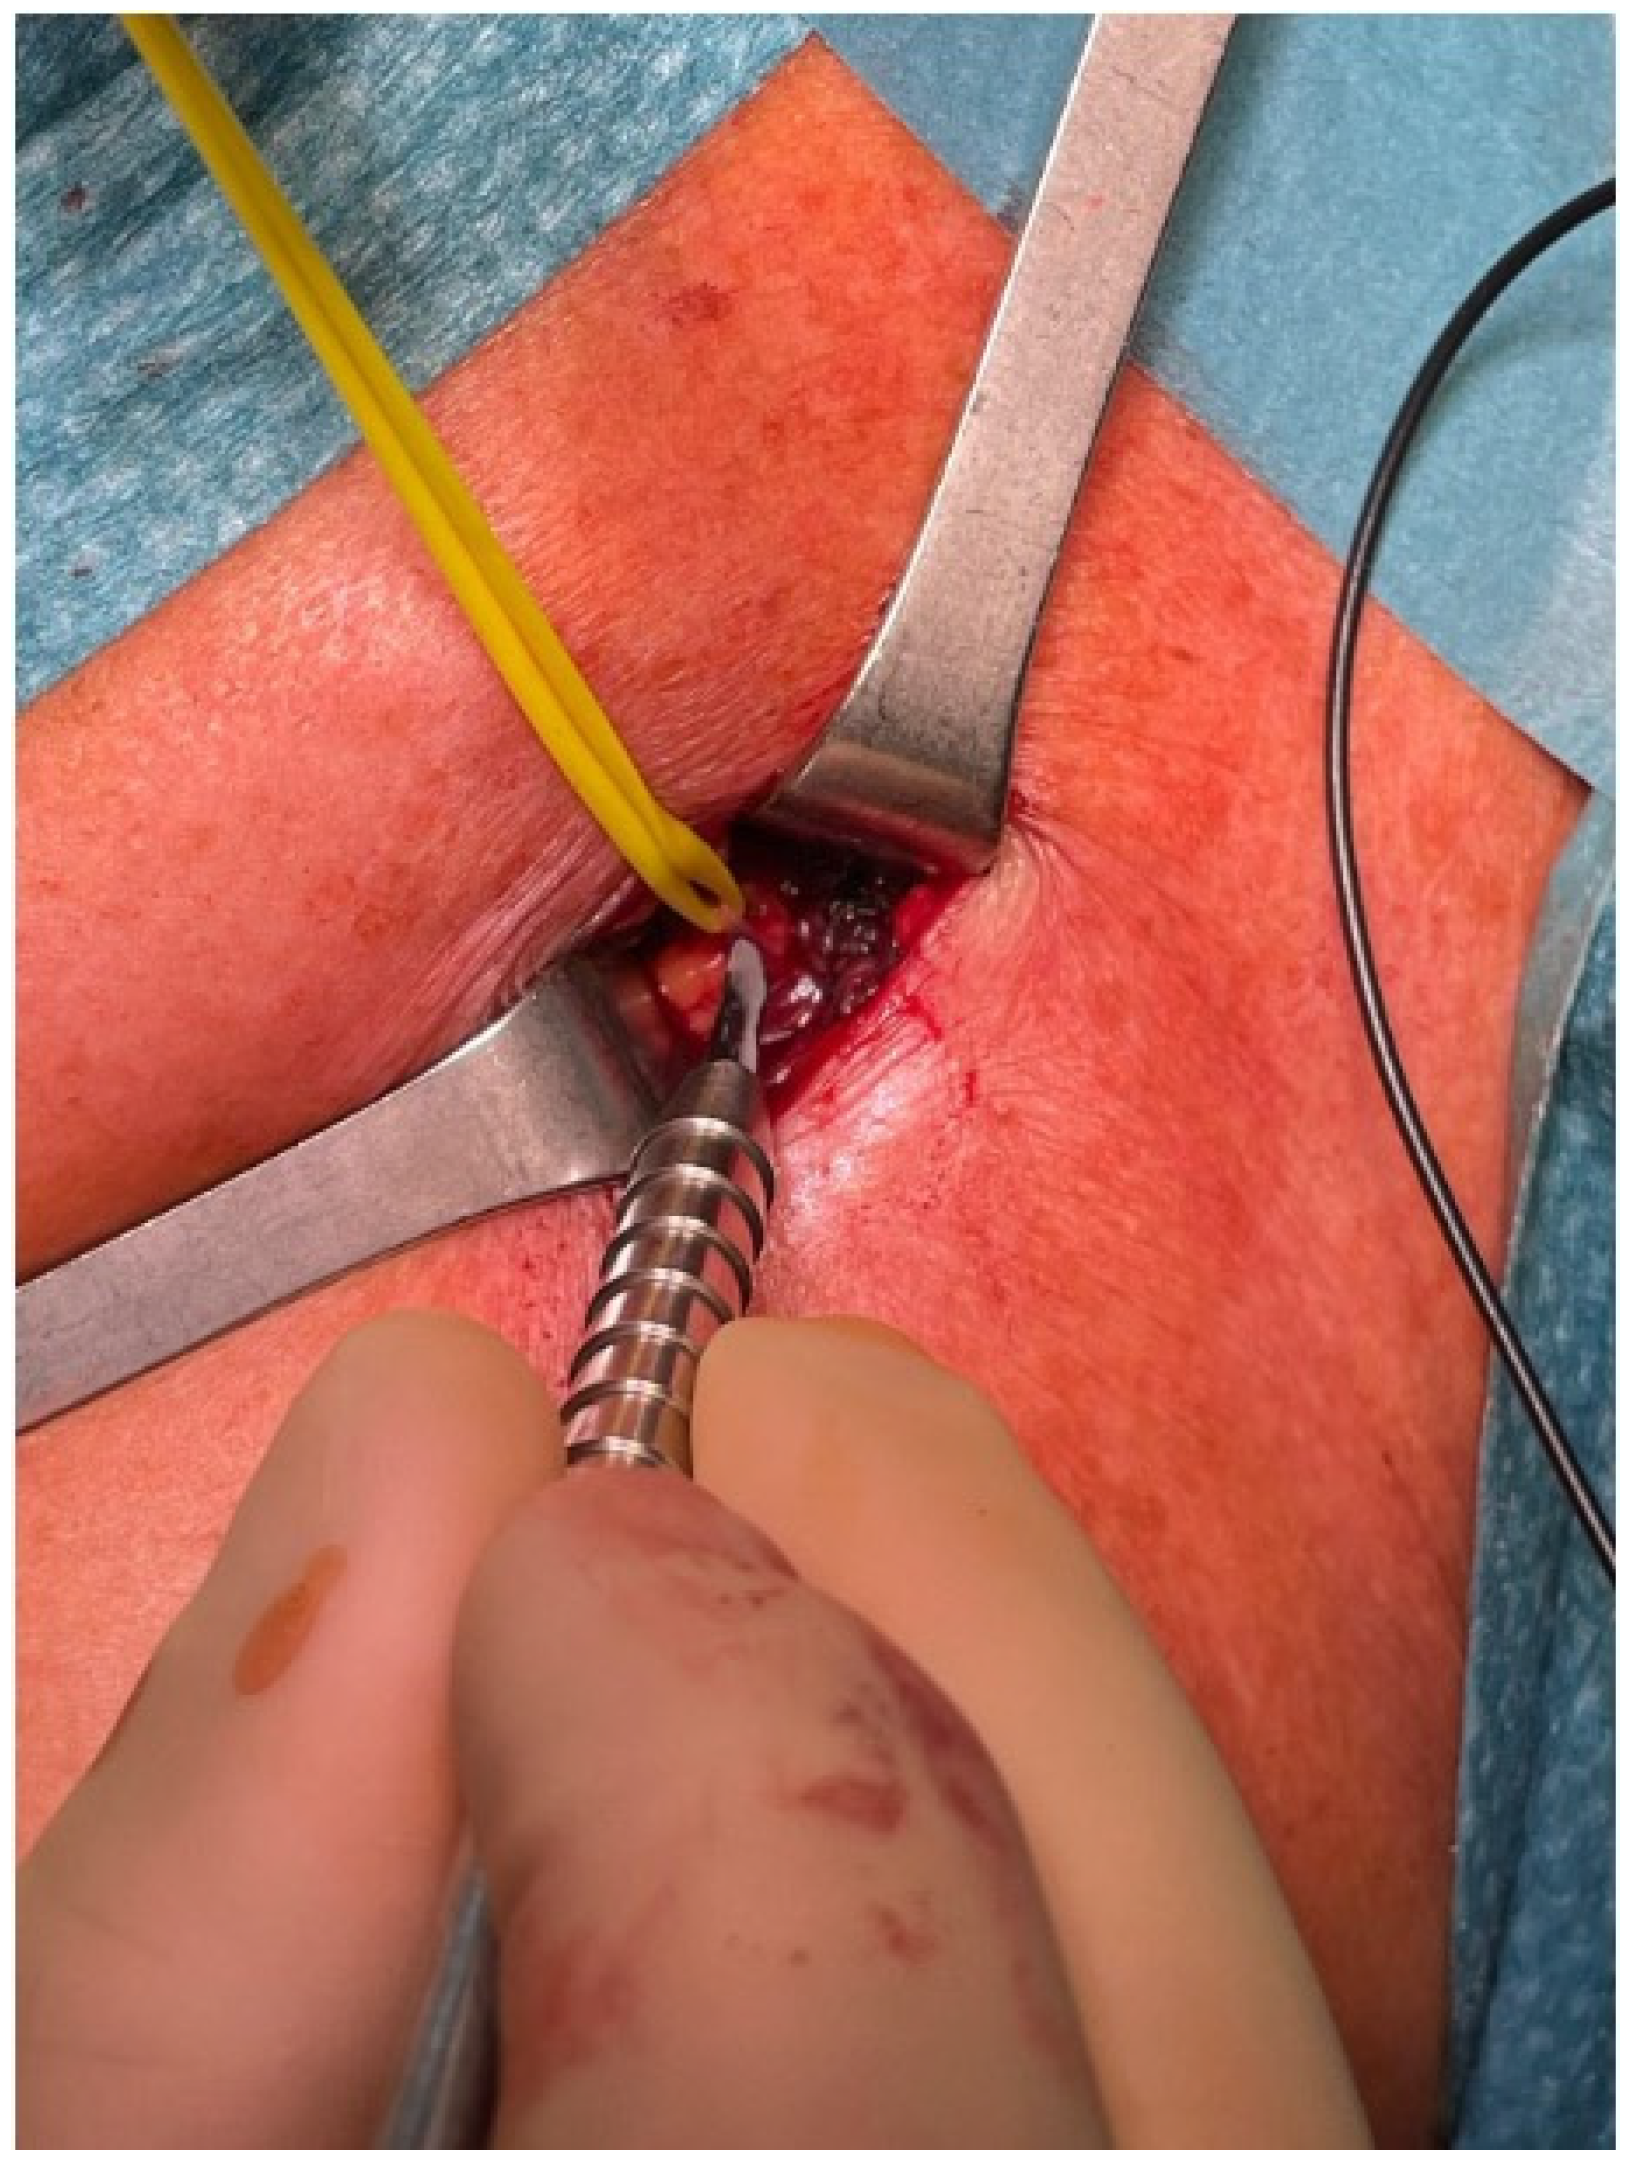

3.4. Exposure

3.5. Selective Peripheral Neurectomy